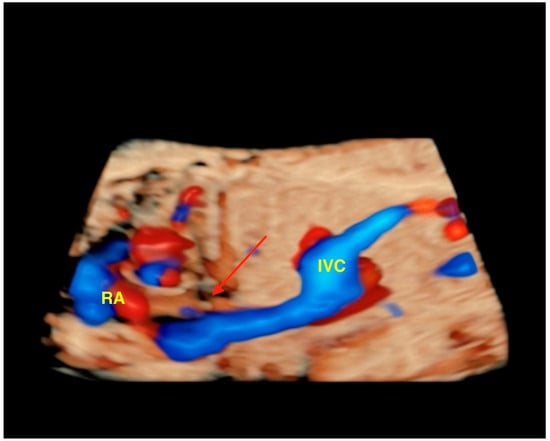

- Tie, H.X.; Ma, B.; Zhang, D.C.; Li, T.G. Prenatal diagnosis of fetal inferior vena cava malformation using HDlive flow combined with spatiotemporal image correlation. Echocardiography 2022, 39, 685–690. [Google Scholar] [CrossRef]